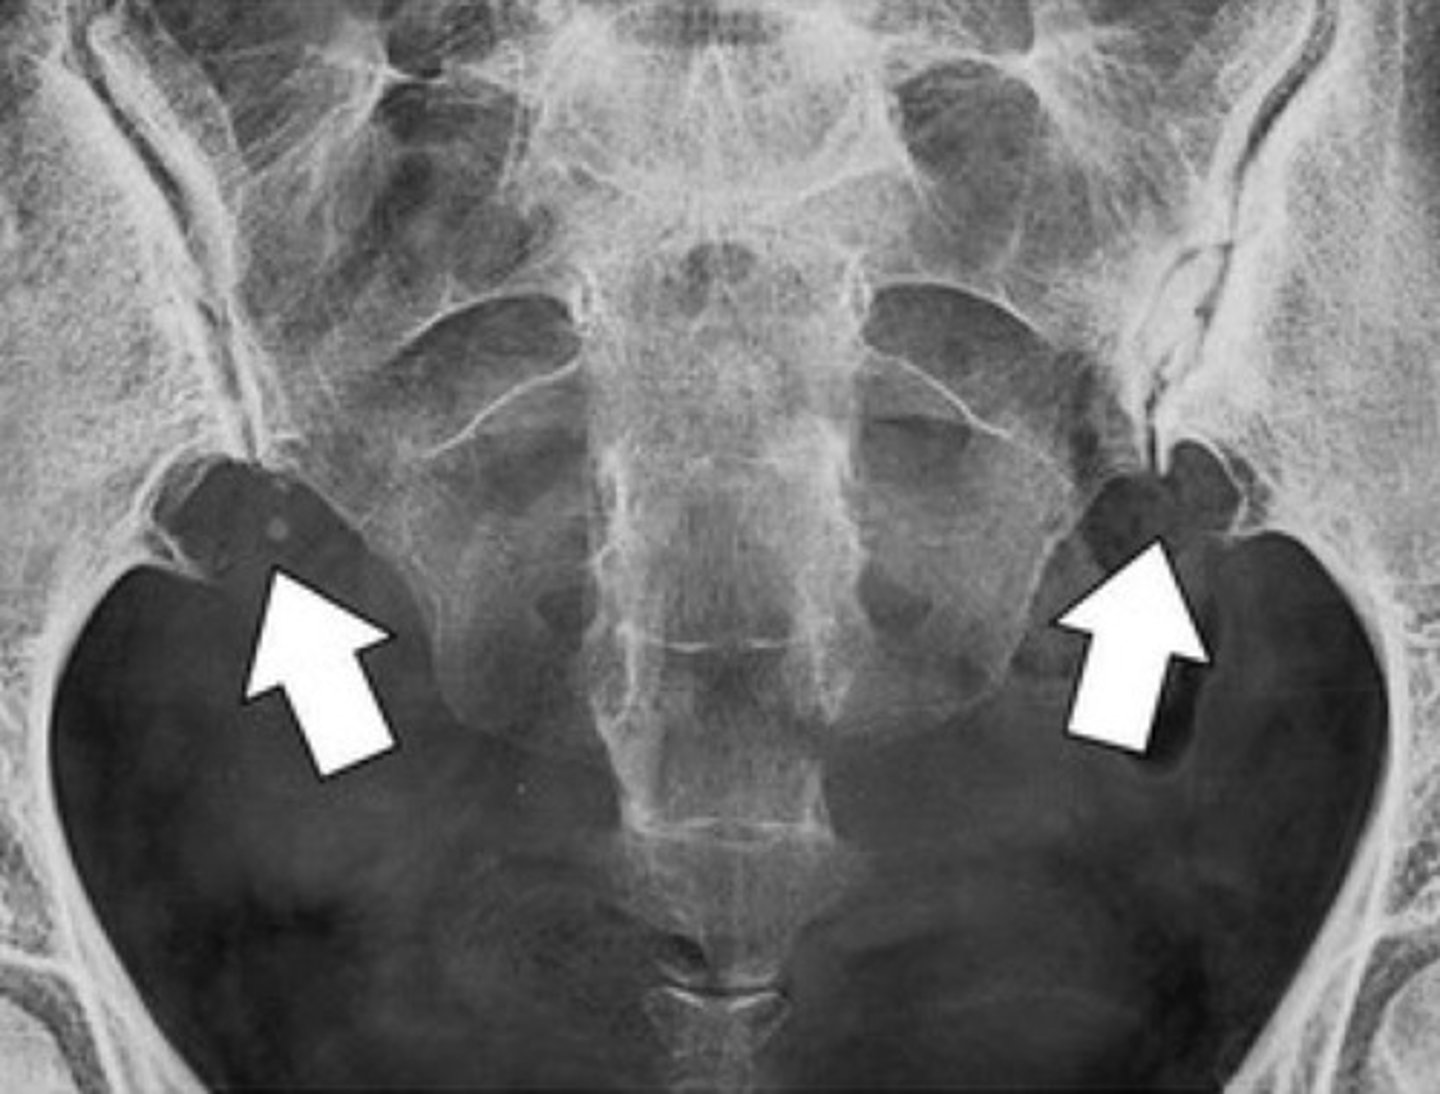

Femoral Herniation Pits

Notice denser, cortical bone around the pit

Clinical Significance of Femoral Herniation Pits

Incidental findings with no clinical significance = "leave it alone lesion"

Pits may enlarge over time